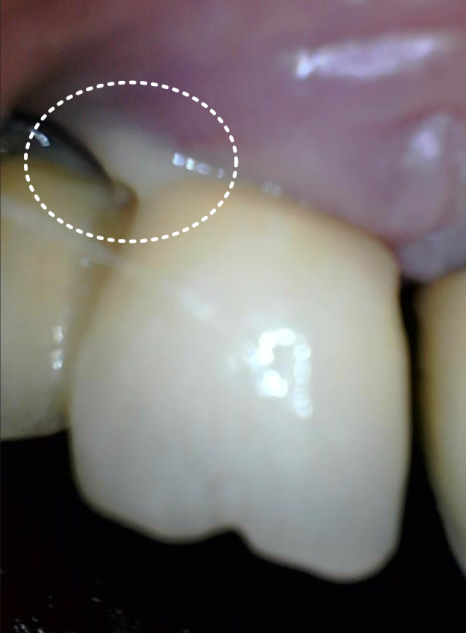

정밀 사진을 보니

어금니 쪽 임플란트(#46, 47) 주변 잇몸뼈가

251118

염증(임플란트 주위염) 때문에

많이 녹아 있는 상태였는데요.

임플란트 옆에 도자기로 씌워둔 치아(#45)의

보철물이 깨져 있었는데,

그 틈으로 음식물이 계속 끼어 들어가면서

치아 뿌리 깊숙이 충치가 생긴 상태였어요.